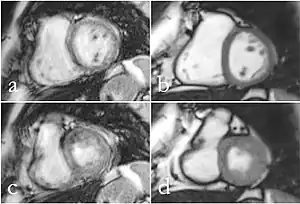

Cardiac MRI

Although applications of real-time MRI cover a broad spectrum ranging from non-medical studies of turbulent flow[26] to the noninvasive monitoring of interventional (surgical) procedures, the most important application making use of the new capabilities is cardiovascular imaging.[1] Previous cardiac MR (CMR) used cine techniques to capture the periodic motion of the heart. However, this is not feasible for patients with arrhythmia, where the cardiac cycle is unpredictable.[27] With the new method it is possible to obtain movies of the beating heart in real time with up to 50 frames per second during free breathing and without the need for a synchronization to the electrocardiogram.[28] A study performed by Laubrock et al.[27] demonstrated that RT-MRI produced higher quality images with a higher SNR than cine CMR with a bSSFP sequence and radial k-space sampling. RT-MRI also removes the need for breath-holding while imaging, leading to a more comfortable experience for the patient as well.[27]